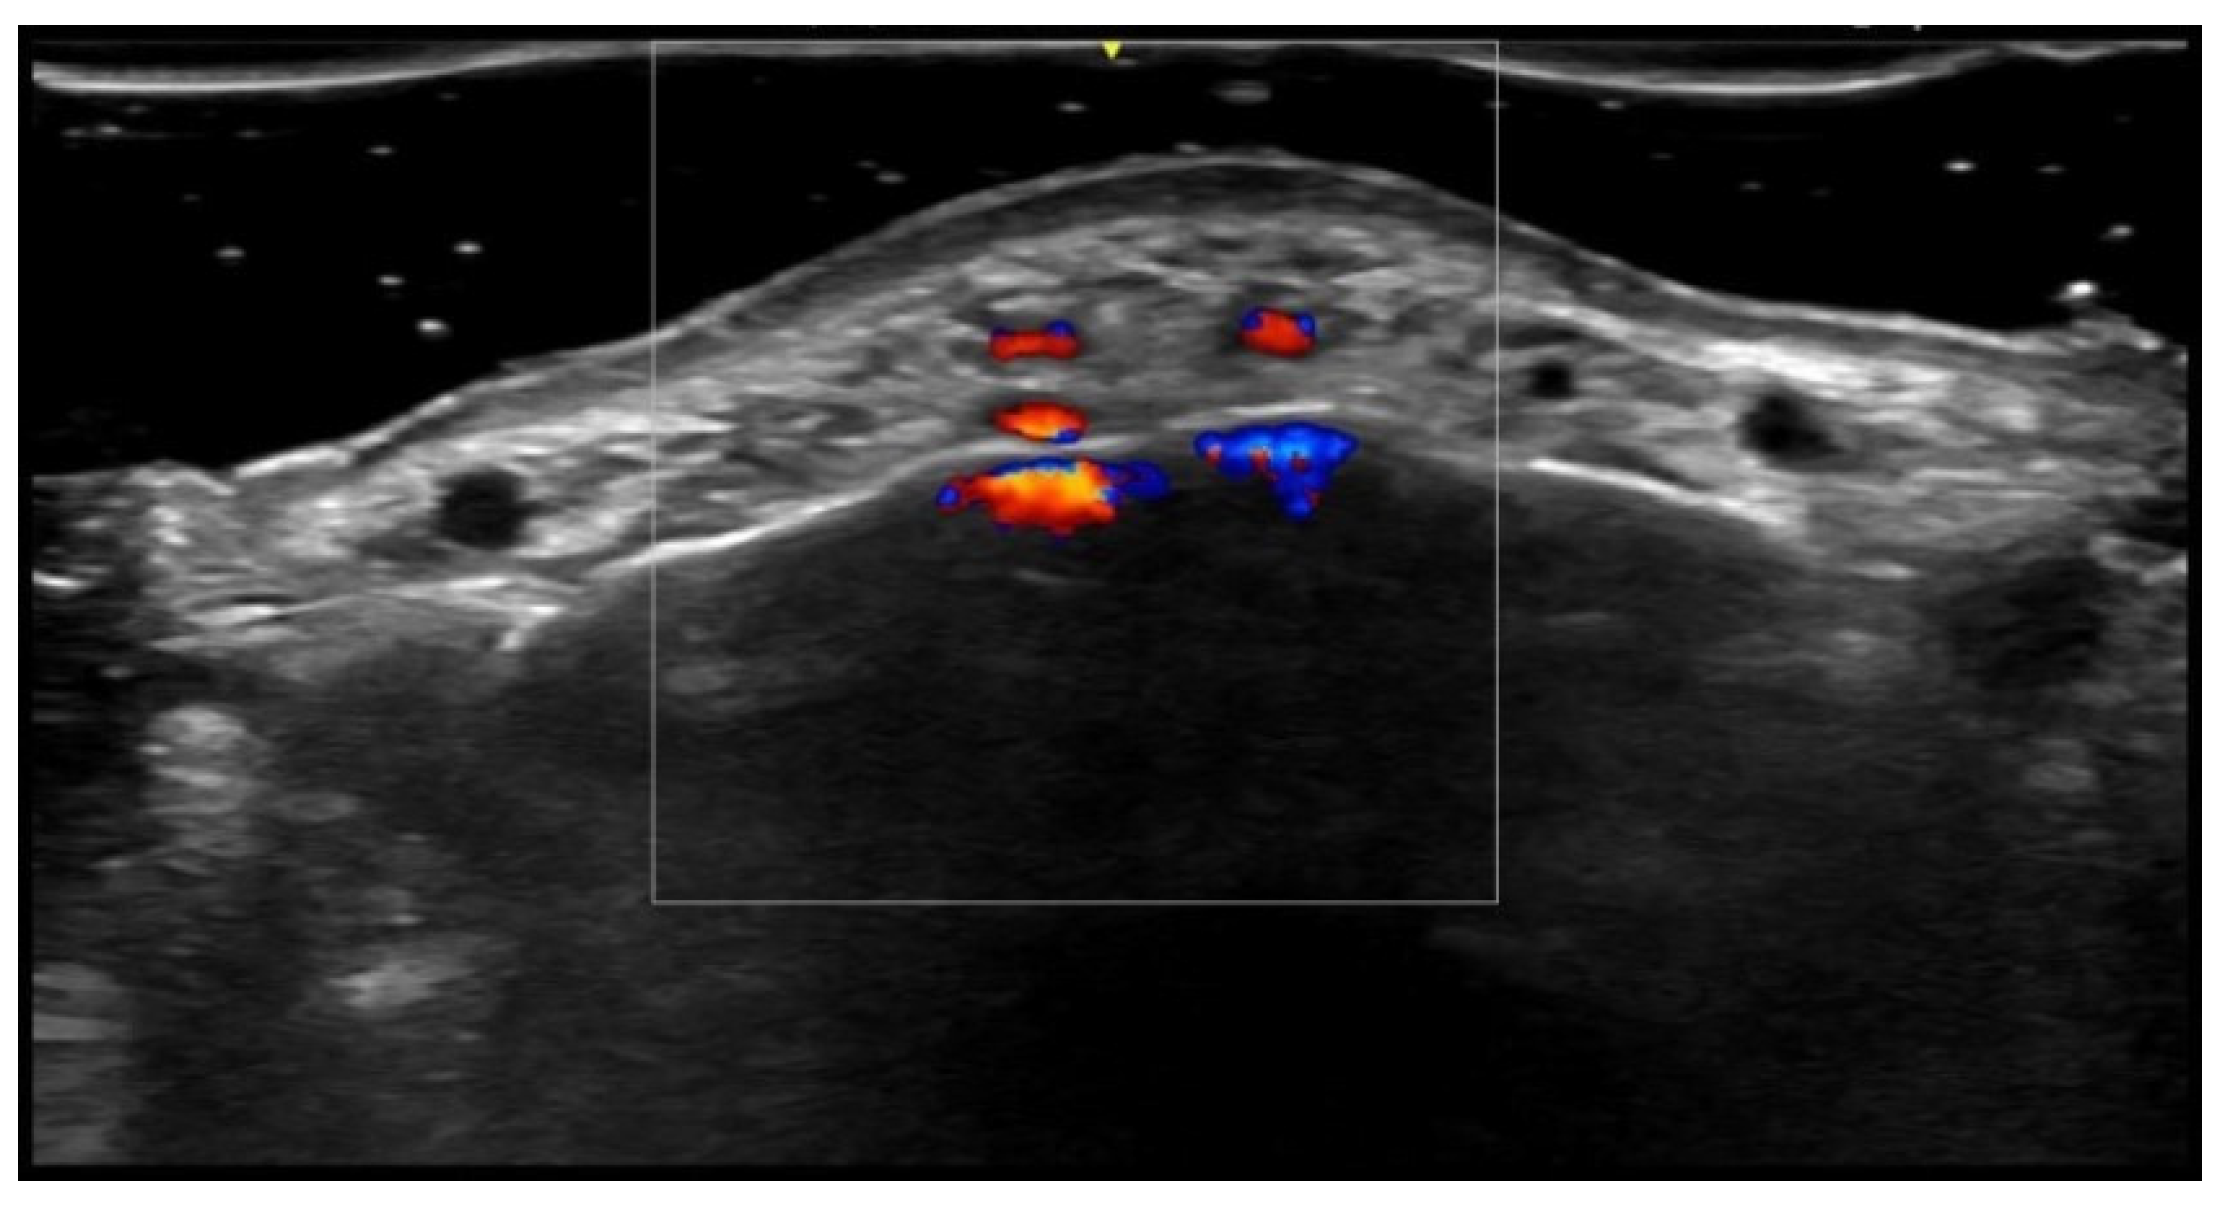

- Velthuis, P.J.; Jansen, O.; Schelke, L.W.; Moon, H.J.; Kadouch, J.; Ascher, B.; Cotofana, S. A Guide to Doppler Ultrasound Analysis of the Face in Cosmetic Medicine. Part 1: Standard Positions. Aesthetic Surg. J. 2021, 41, NP1621–NP1632. [Google Scholar] [CrossRef]

- Vasconcelos-Berg, R.; Izidoro, J.F.; Wenz, F.; Müller, A.; Navarini, A.A.; Sigrist, R.M.S. Doppler Ultrasound-Guided Filler Injections: Useful Tips to Integrate Ultrasound in Daily Practice. Aesthetic Surg. J. 2023, 43, 773–783. [Google Scholar] [CrossRef]